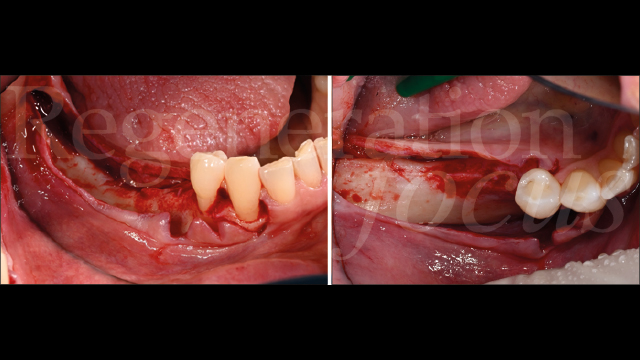

Il follow-up a 2 e 4 settimane ha documentato la guarigione per prima intenzione. A 6 mesi, la CBCT ha evidenziato eccellente integrazione dell’innesto con ottimale densità ossea (Fig. 10). La seconda fase chirurgica ha previsto la rimozione della mesh e l’inserimento simultaneo di due impianti tissue level (3.7 x 10 mm plat. 3.7 in sede 45; 3.7 x 8 mm plat. 4.5 in sede 47) caratterizzati da un design transmucoso concavo di 1.8 mm con superficie anodizzata (Matrix Line, TRI Dental Implants) (Fig. 11). Il torque di inserimento di 45 Ncm ha confermato l’ottima qualità ossea.

Durante la stessa seduta, valutato il sottile spessore mucoso, si è proceduto alla modificazione del fenotipo tissutale. Una matrice di collagene (Geistlich Fibro-Gide®) è stata posizionata con tecnica “a poncho”: la matrice è stata bucata in corrispondenza delle viti di guarigione degli impianti e posizionata sulla cresta alveolare, permettendo di ispessire il complesso dei tessuti molli sovracrestali sia verticalmente che orizzontalmente (Fig. 12).